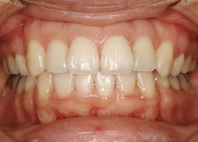

前歯のでこぼこと八重歯の治療を希望されて来院されました。

※左右でカメラが異なるので少し明るさ・濃さに違いがあります。ご了承ください。

左:初診時、右:治療開始7ヶ月(治療途中)

上は裏側の装置、下は表側の装置で治療を行っています。上の装置が目立たないだけでも患者さまの気持ち的な負担は少ないですよね。

少し口を開いて撮影したもの。治療開始7ヶ月で上の八重歯、下の歯のでこぼこがかなり改善したので患者さまにとても喜んで頂いています。

上の歯並びの状態を見た写真です。初診時は前歯の真ん中が右へかなりズレていましたが、解消しています。前歯の真ん中の改善、出っ歯の改善にはミニインプラントを使用しています。とても効果的な手段のひとつです。

下前歯のでこぼこもだいぶ治っています。

上前歯は最初、出っ歯でしたが上前歯は下の前歯まで下がっています。

スマイルです!左は初診時(ピントが合っていなくてショックです…)